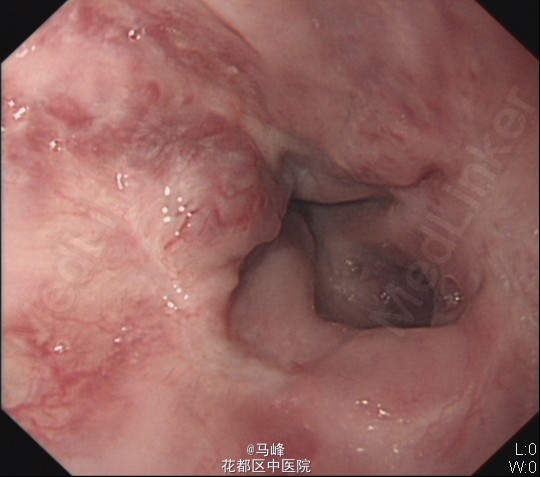

老年男性,主诉:发现乙肝肝硬化7月,返院复查。既往有乙型肝炎病史,目前已服用“博路定 0.5mg qn”抗病毒治疗4月。 现病史:患者7月前外院诊断“乙肝肝硬化”。后为求进一步诊治,来我科住院治疗,分别于2014-9-9、2014-10-21及2015-3-20在我院行胃镜下“食管重度静脉曲张套扎术”治疗,术后无诉不适,好转出院。

入院后予抗病毒、补充营养等对症支持治疗,排除禁忌症后于13/5在无痛胃镜下行食管重度静脉曲张套扎术,术后予加强护胃治疗。